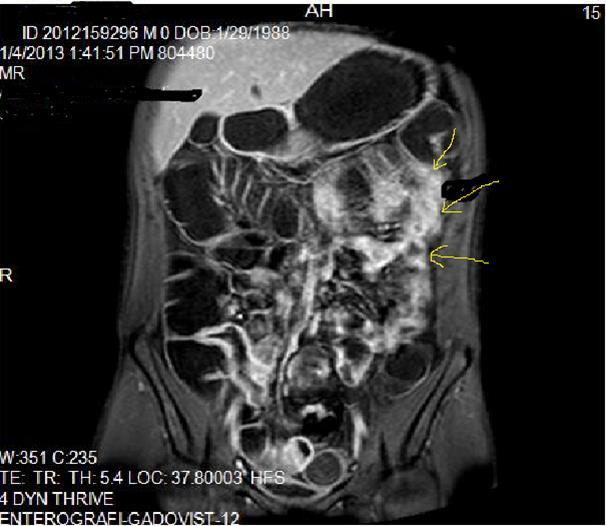

Figure 2a.Concentric luminal narrowing, mural and transmural involvement of terminal ileum due to Crohn’s disease in T2W coronal sequence after OCA application.

Figure 2b.Curvi-lineer, diffuse peripheral enhancing bowel wall in the terminal ileum on axial T1W post-contrast image.

Figure 3a-3b-3c.Diffuse mucosal involvement and extreme luminal narrowing in the terminal ileum due to Crohn’s disease on T2W coronal sequence after OCA administration, stricture and string sign near ileo-ceccal valve in Figure 3b.